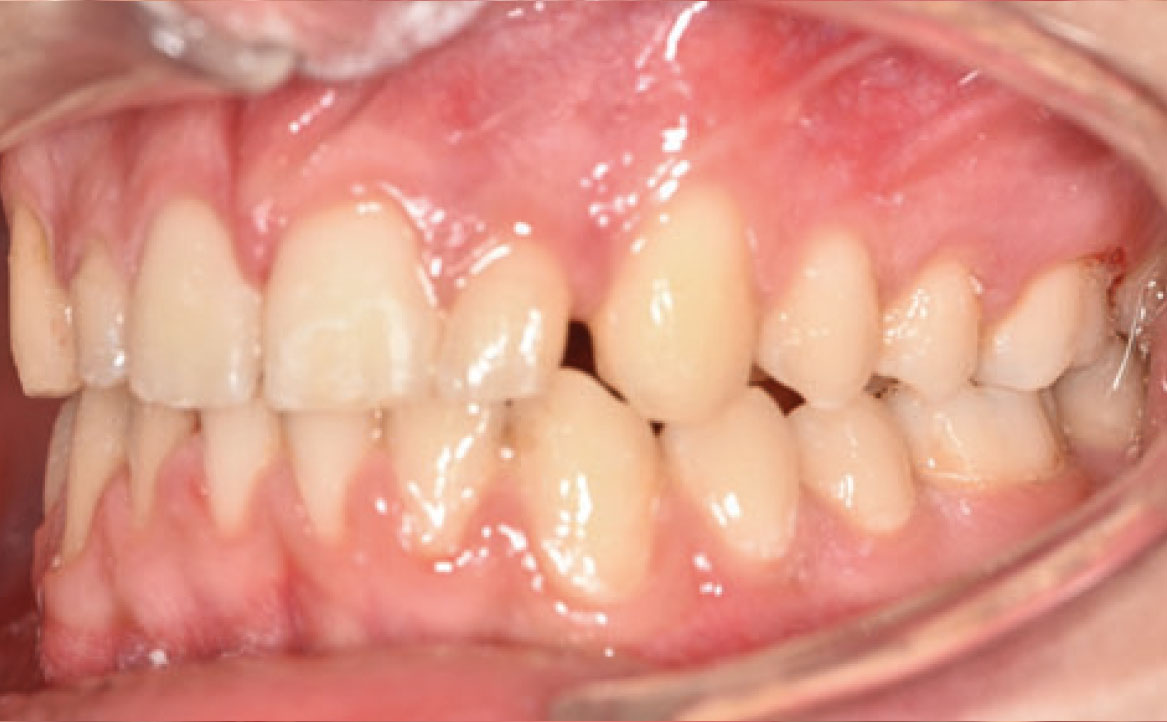

Il paziente si è presentato per la sua prima visita presso il reparto di Odontoiatria e Protesi Dentaria dell’Ospedale Vita-Salute San Raffaele diretto dal prof. E. F. Gherlone. All’esame obiettivo era evidente una malocclusione scheletrica e dentale di classe II associata a morso profondo e lieve affollamento anteriore superiore. In particolare, sono stati segnalati: rapporti occlusali di classe II, morso profondo, perdita di overjet, contrazione dell’arcata superiore e inferiore con leggero affollamento (fig. 1a-f). La richiesta del paziente era quella di migliorare l’estetica dei denti anteriori con allineatori invisibili di tipo Invisalign. Tuttavia, sia il paziente che il genitore sono stati informati che, per ragioni di efficacia e risoluzione del problema, era necessario agire anche a livello di funzionalità e risoluzione della malocclusione.

In primo luogo, sono stati prescritti entrambi gli esami radiografici ortodontici: OPT e teleradiografia latero-laterale del cranio (fig. 2a-b). Successivamente, in accordo con il genitore, è stata concordata una terapia ortodontica in due tempi. L’inizio della terapia è stato effettuato con Carriere Motion ed elastici di classe II, con l’obiettivo di migliorare la classe molare (fig. 2c-e).